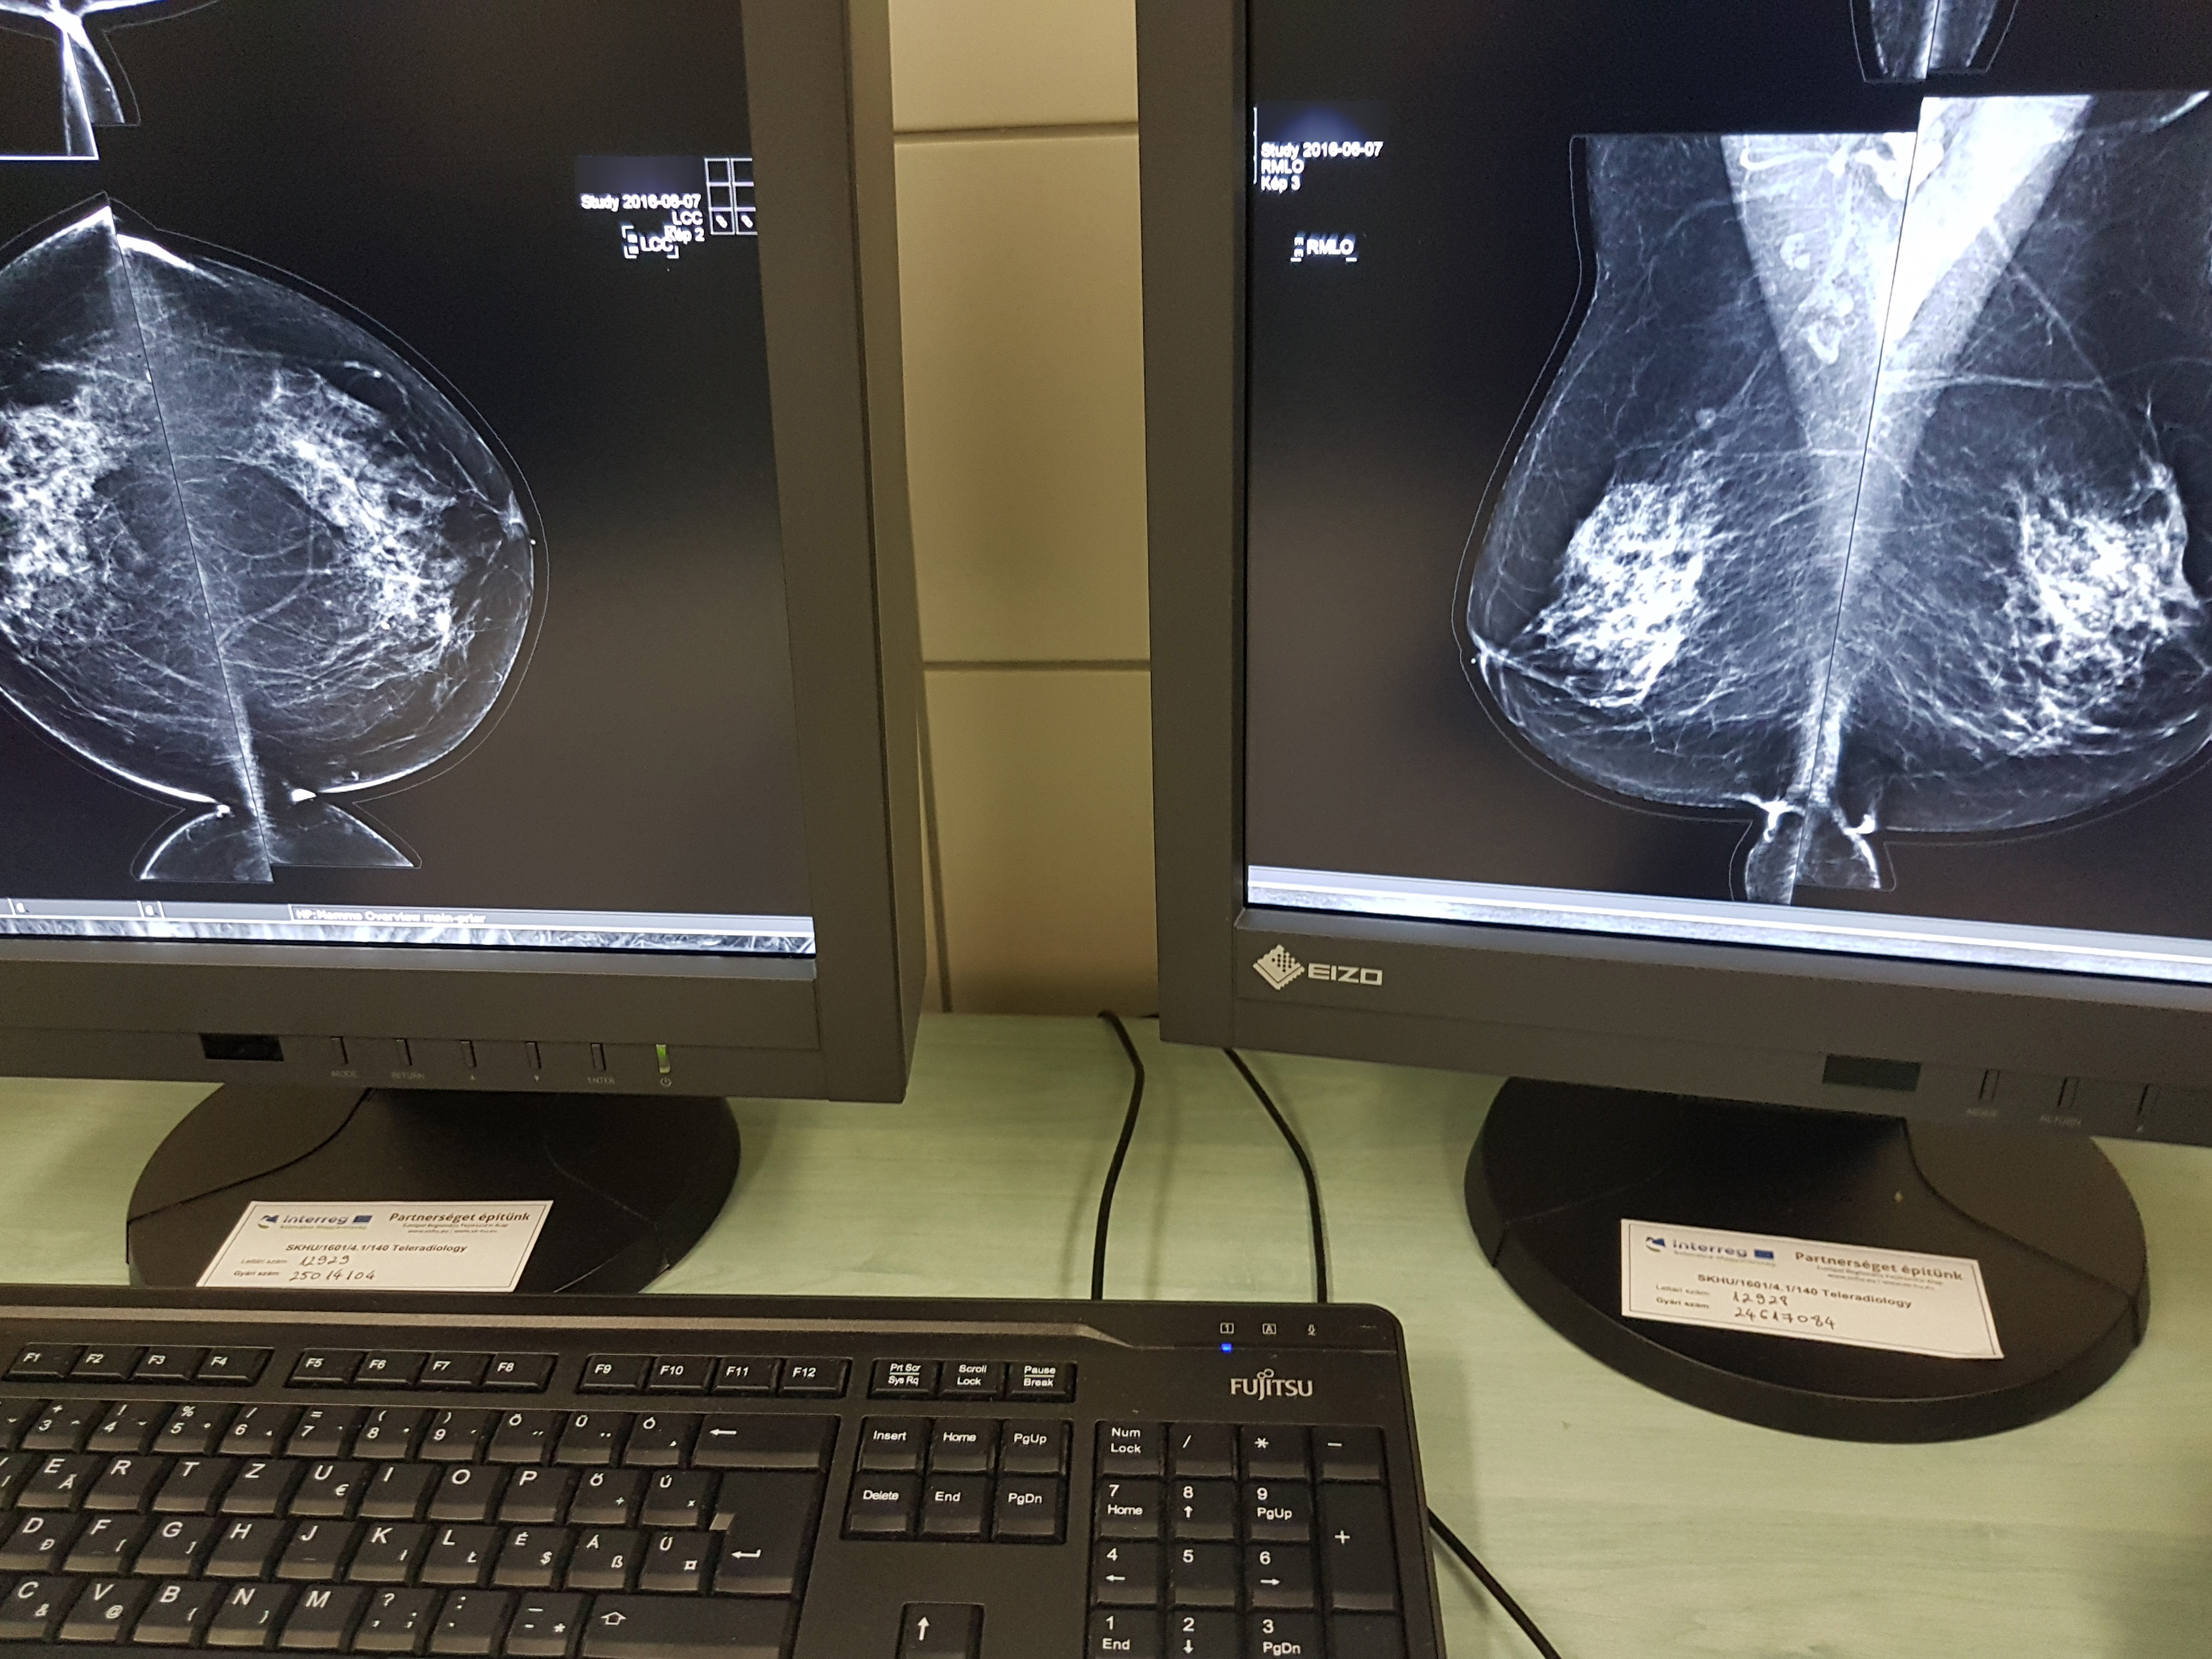

A fejlesztés részeként Miskolcon a már meglévő PACS (Picture Archiving and Communication System) rendszer fejlesztéséhez, míg Királyhelemcen a PACS rendszer bevezetéséhez szükséges informatikai hardver, valamint szoftver elemeket szereztek be. A PACS egy olyan technológia, amely képes kezelni, archiválni, megjeleníteni és megosztani a képi dokumentációt, például a röntgen, a mágneses rezonancia és a CT képeket.

Kostyál László, a Borsod-Abaúj-Zemplén Megyei Központi Kórház és Egyetemi Oktatókórház Képalkotó Diagnosztikai Centrumának osztályvezető főorvosa hangsúlyozta: a szlovák részről nagyobb beruházást jelentett a projekt, „ugyanis ők egy új gépet, egy teljesen új technikát kaptak“, a Borsod megyei egészségügyi intézményben a már meglévő technikának a modernizálása és a felgyorsítása volt a cél, ennek részeként készült 13 új leletező állomás az osztályra.

A fejlesztésnek köszönhetően a képek gyorsan „lejönnek“, azonnal megtekinthetők. Nagyon fontos lenne, hogy a szlovák munkatársak itt - Miskolcon - is gyakorlatot, tudásanyagot szerezzenek, hiszen a megyei kórházban naponta mintegy 130 CT vizsgálat történik, ott pedig 10-15. Eddig mintegy 60-80 leletanyag érkezett Királyhelmecről, itt nem is a mennyiség, hanem a képek minősége, felbontása volt a fontos, hogy kiváló, tökéletesen kiértékelhető legyen valamennyi – tette hozzá.